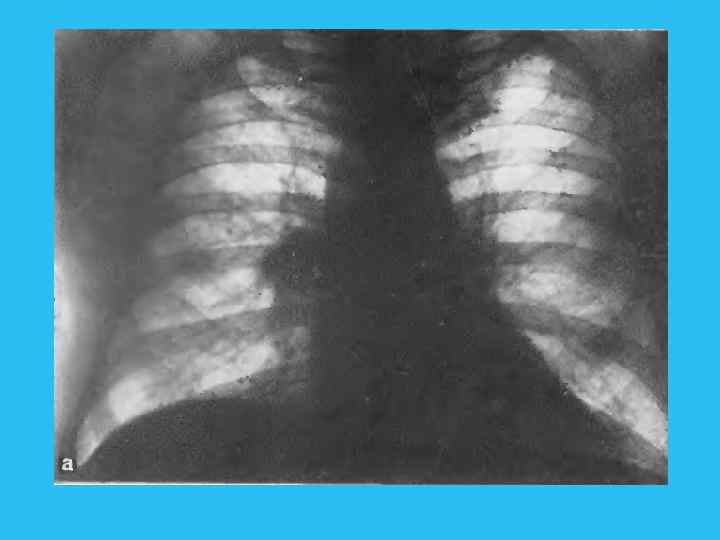

Рис. 245. Ателектаз язычка. Узел в корневой зоне отчетливо не виден. а — прямая рентгенограмма; б — бокивая томограмма; опухолевый узел в корневой зоне отчетливо не виден; в — томограмма. Позиция PS (45°). Опухолевый узел обрастает все разветвления верхне долевого, язычновогои промежуточного бронхов.